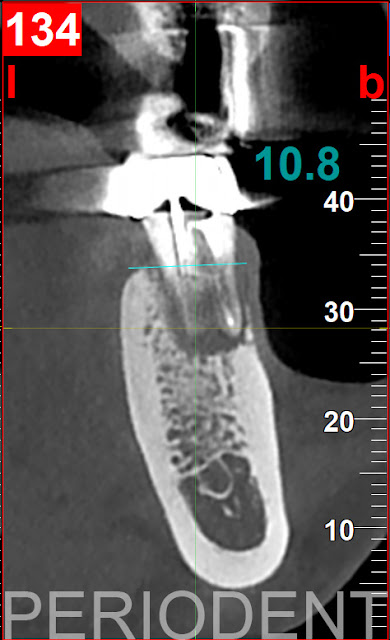

1. 患者左下第一大臼齒有Gumboil產生,近心牙根有6~7釐米深的狹窄囊袋,電腦斷層檢查也懷疑牙根斷裂

10. 一年數位取模,配合電腦斷層影像,製作植牙手術導版